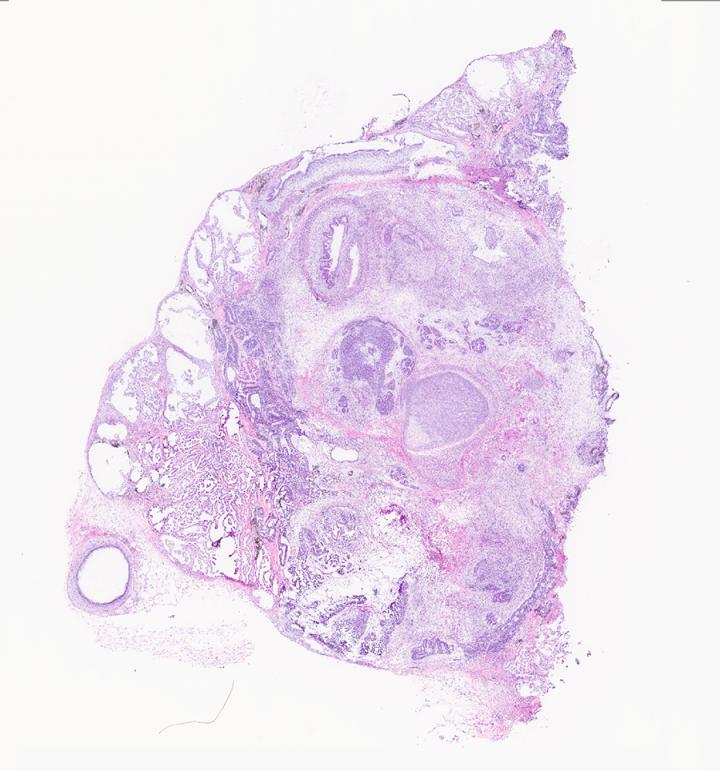

image: Histology image of a teratoma

Teratomas-- which mean "monstrous tumors" in Greek--are tumors made up of different tissues such as bone, brain, hair and muscle. They form when a mass of stem cells differentiates uncontrollably, forming all types of tissues found in the body. Teratomas are generally considered an undesired byproduct of stem cell research, but UC San Diego researchers found an opportunity to study them as a model for human development.

"We've been fascinated with the teratoma for quite a while," said Prashant Mali, a professor of bioengineering at the UC San Diego Jacobs School of Engineering. "Not only is the teratoma an intriguing tumor to look at in terms of the diversity of cell types, but it also has regions of organized tissue-like structures. This prompted us to explore its utility in both cell science and cell engineering contexts."

"There's no other model like it. In just one tumor, you can study all of these different lineages, all of these different organs, at the same time," said Daniella McDonald, an M.D/Ph.D. candidate in Mali's lab and co-first author of the study. "Plus, it's a vascularized model, it has a three-dimensional structure and it's human-specific tissue, making it the ideal model for recreating the context in which human development happens."